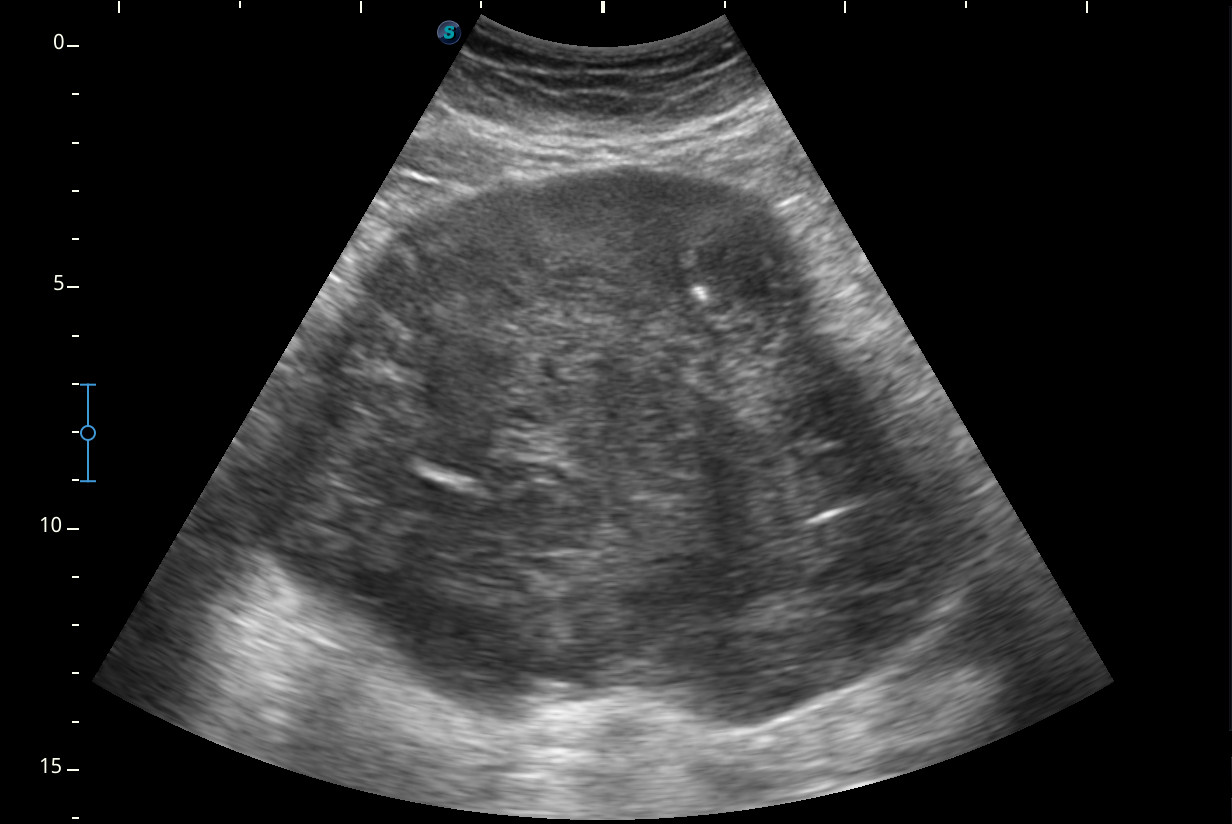

Se visualiza una masa heterogénea de unos 10 x 13 cm aproximadamente de diámetro con posibles focos necróticos y captación Doppler color, de dudosa organodependencia, que podría corresponder a un sarcoma retroperitoneal.